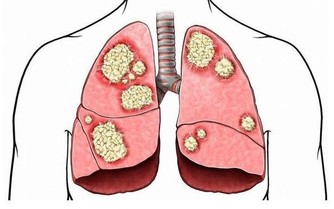

大蒜:殺菌預防胃癌

英國權威醫學雜誌上刊登了一個研究報告,經常吃大蒜能夠降低胃癌的死亡率。我們都知道幽門螺桿菌感染是胃癌的致病因素之一,而經常吃大蒜有助於預防胃癌的發生。因為大蒜中的大蒜素具有一定的殺菌、防癌功效,抑制有利於腫瘤生長的酶活性。所以本身有幽門螺桿菌感染的朋友不妨多吃一些大蒜,能預防胃癌發生。